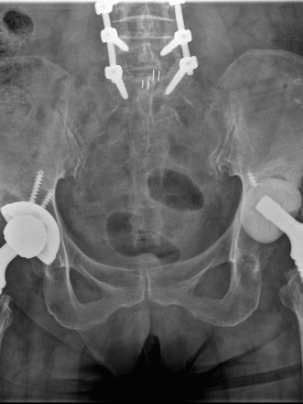

74岁的李大妈(化名),为我们讲述了她的故事:2021年6月,李大妈因为双侧股骨头坏死,行全髋关节置换术,术后恢复良好,日常生活行动自如。

2023年1月,李大妈感左侧髋部疼痛明显,活动受限,复诊提示左侧髋关节髋臼松动翻转,假体上移。

经过前期的治疗,现在左侧髋关节疼痛是影响李大妈生活质量的最大问题。通过对本次入院后髋关节CT的再次评估,张海军主任发现患者左侧髋臼骨缺损比3月前明显增多,普通假体无法完成手术,决定采用3D打印新技术评估髋臼缺损、模拟手术方案,经过3D打印模型和计算机测量评估,决定使用钽金属垫块和多孔钽杯重建髋臼。